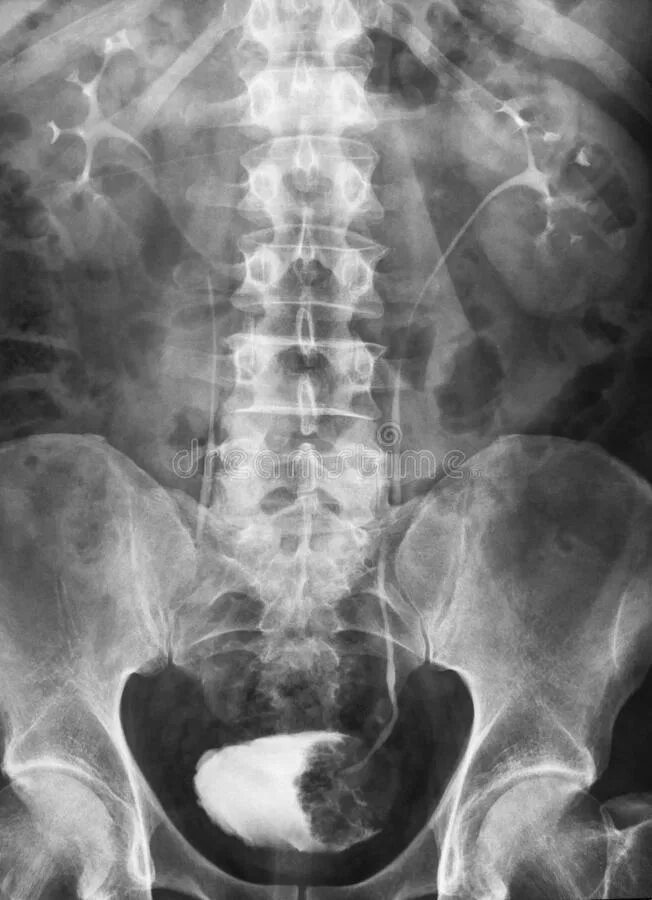

После урографии